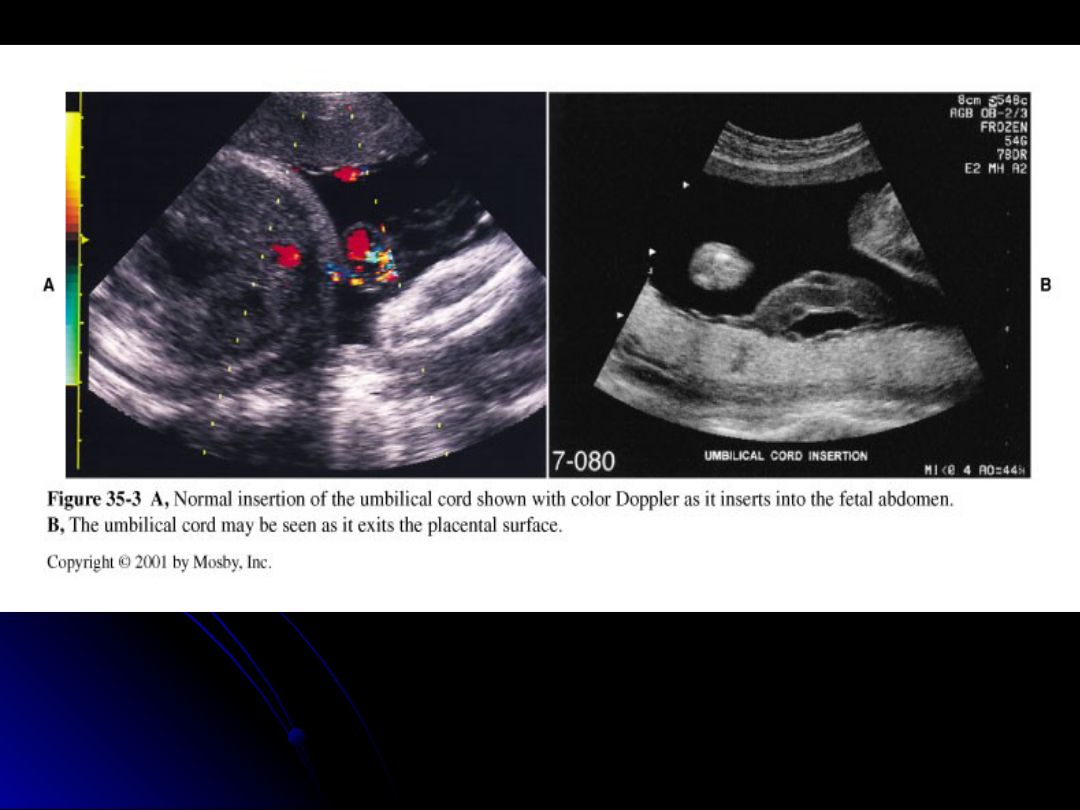

Which one of the following occurs when the cord inserts into the membranes before it enters the placenta?

velamentous insertion